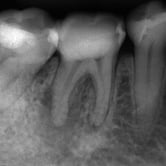

Pulpitis Reversible

La pulpitis reversible es una inflamación leve de la pulpa dental, generalmente causada por caries o una lesión menor.

Los pacientes suelen experimentar sensibilidad al frío o al calor, pero el dolor desaparece rápidamente.

Si se trata adecuadamente, la pulpa puede sanar sin complicaciones. Es importante acudir al dentista para evitar que progrese a una pulpitis irreversible.